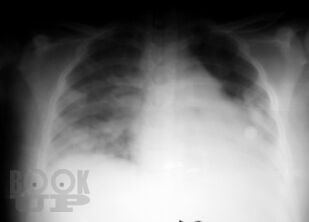

В учебно-методическом пособии представлены этиология, патогенез, клиника, осложнения, лечение, комплексная ультразвуковая, рентгенологическая, мультиспиральная компьютерная томографическая семиотика острого гематогенного остеомиелита у детей. Пособие раскрывает современные подходы ранней диагностики острого гематогенного остеомиелита у детей и предлагает оптимальный алгоритм ранней диагностики.